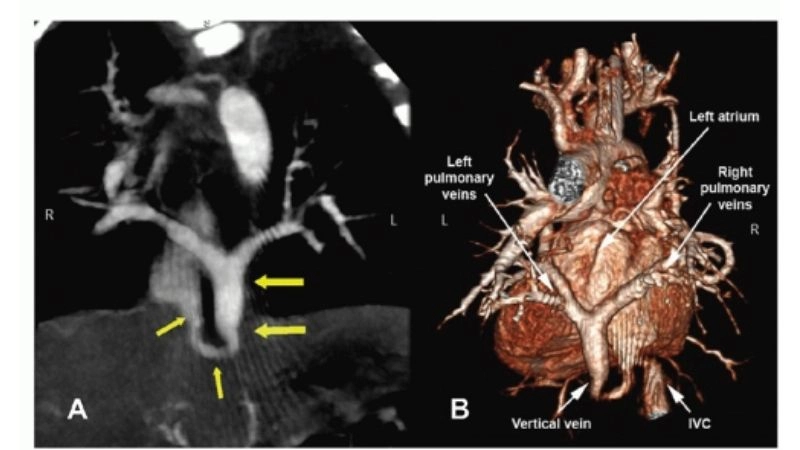

Images visual examples of total anomalous pulmonary venous return (TAPVR)

Total anomalous pulmonary venous return (TAPVR) is a rare congenital heart defect where pulmonary veins drain into the wrong heart chamber, impairing oxygen delivery and requiring surgical correction.